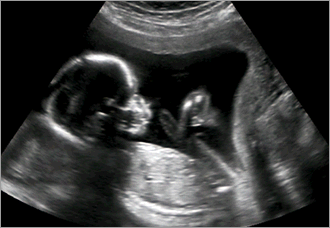

uterus-transplantオハイオ州の著名な非営利医療機関クリーブランド・クリニックが数か月内に子宮の移植手術に踏み切る方針を決めた。

卵巣はあるが先天的に子宮がない女性らに移植する。